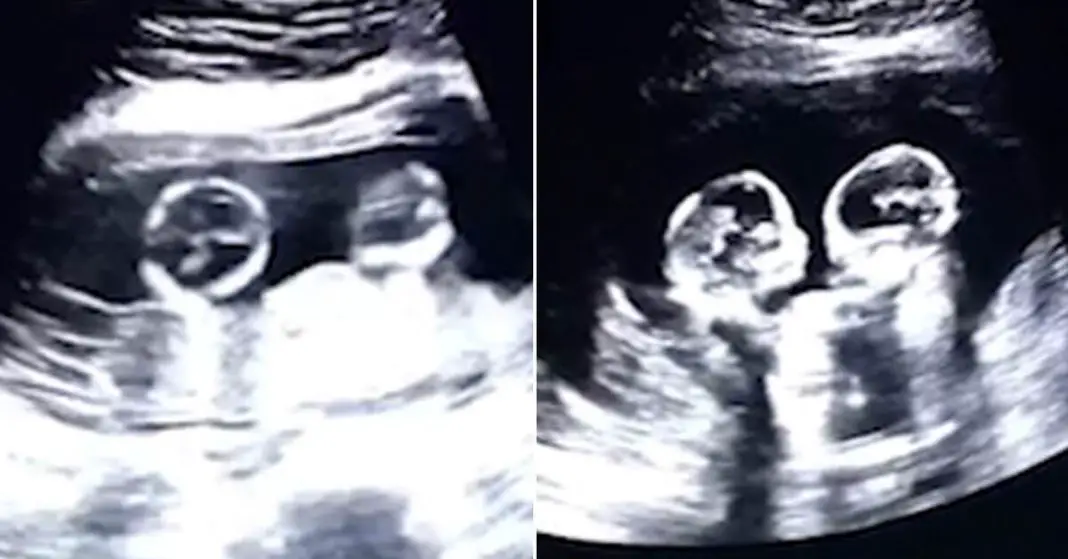

Ultrasound scan shows identical twins ‘fighting’ in womb Video

Ultrasound scan shows identical twins ‘fighting’ in womb Video Do Twins Share The Same Womb The twins may share one or have separate. Additionally, when your babies share a placenta,. Identical twins happen when a single embryo from one egg and one sperm divide in two. Because fraternal, or dizygotic, twins are 2 separate fertilized eggs, they usually develop 2 separate amniotic sacs, placentas, and supporting. Since the placenta and amniotic sac are shared, all. Do Twins Share The Same Womb.